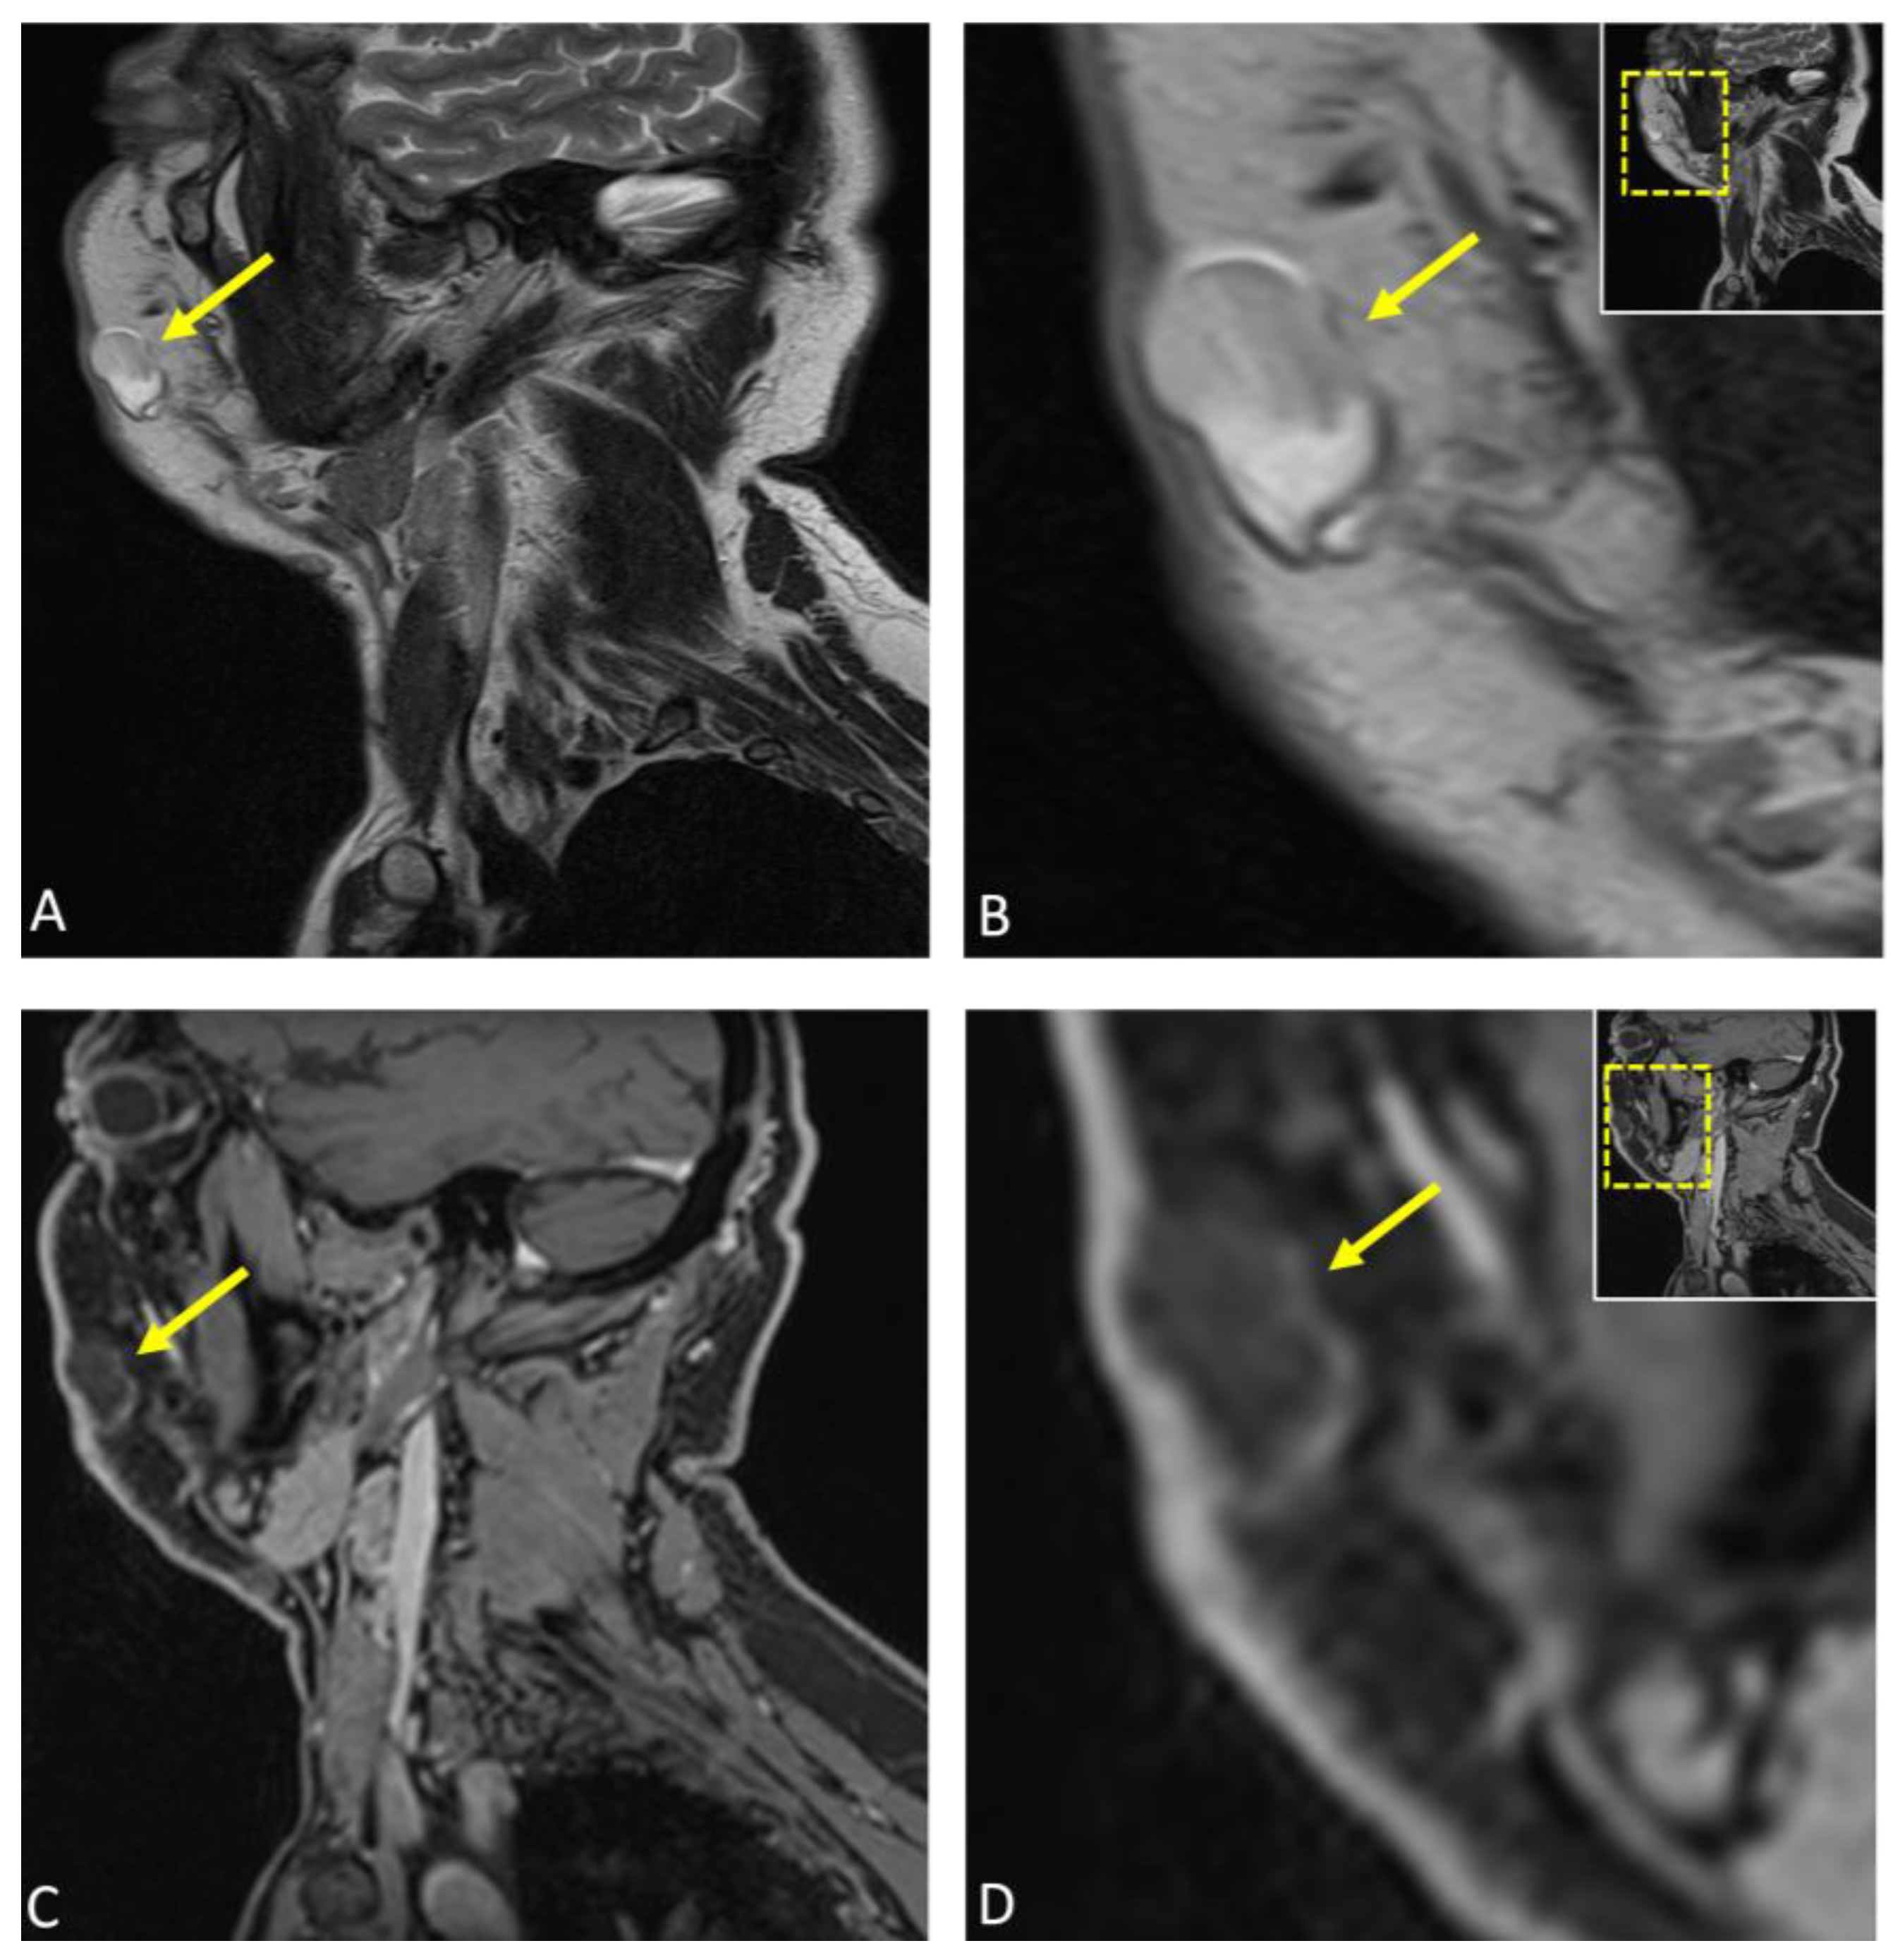

Subsequently, considering the patient’s age and medical history, a comprehensive diagnostic imaging workup was conducted, encompassing both conventional and dental MRI protocols for visualizing the facial skull and suprahyoidal neck using a contrast agent. This approach was undertaken with the objective of attaining a more detailed understanding of the patho-anatomy within the specified region, delineating soft tissues, and characterizing the lesion’s internal composition. The patient underwent MRI at 3 Tesla (MAGNETOM Skyra, release VE11E, Siemens Healthineers, Erlangen, Germany) with the following MRI protocols: Sagittal reconstructions of the lesion are presented in (A) T2-weighted turbo spin echo (TSE) and (C) T1-weighted Dixon MRI, with an enlarged view in (B,D), respectively. The lesion (arrow) measured 24 × 12 × 16 mm and was identified as a well-circumscribed macrocystic mass within the subcutaneous fat of the right cheek, specifically located in the superficial fascia. Mild compression of the levator anguli oris muscle was observed, with broad-based contact between the lesion and the overlying skin. No significant contrast enhancement was noted in the lesion’s capsule, although there was a slight increase in protein concentration and isotropic diffusion restriction, findings consistent with those observed in epidermoid cysts. Perilesional edema was not present. The rest of the examination revealed no abnormalities in the depicted anatomical areas.